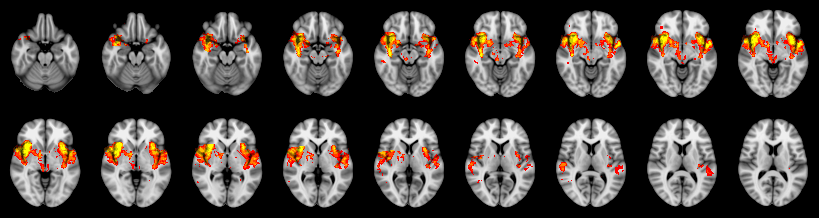

Friston:

IUT/Conjunction/Nichols:

Hotelling T2: